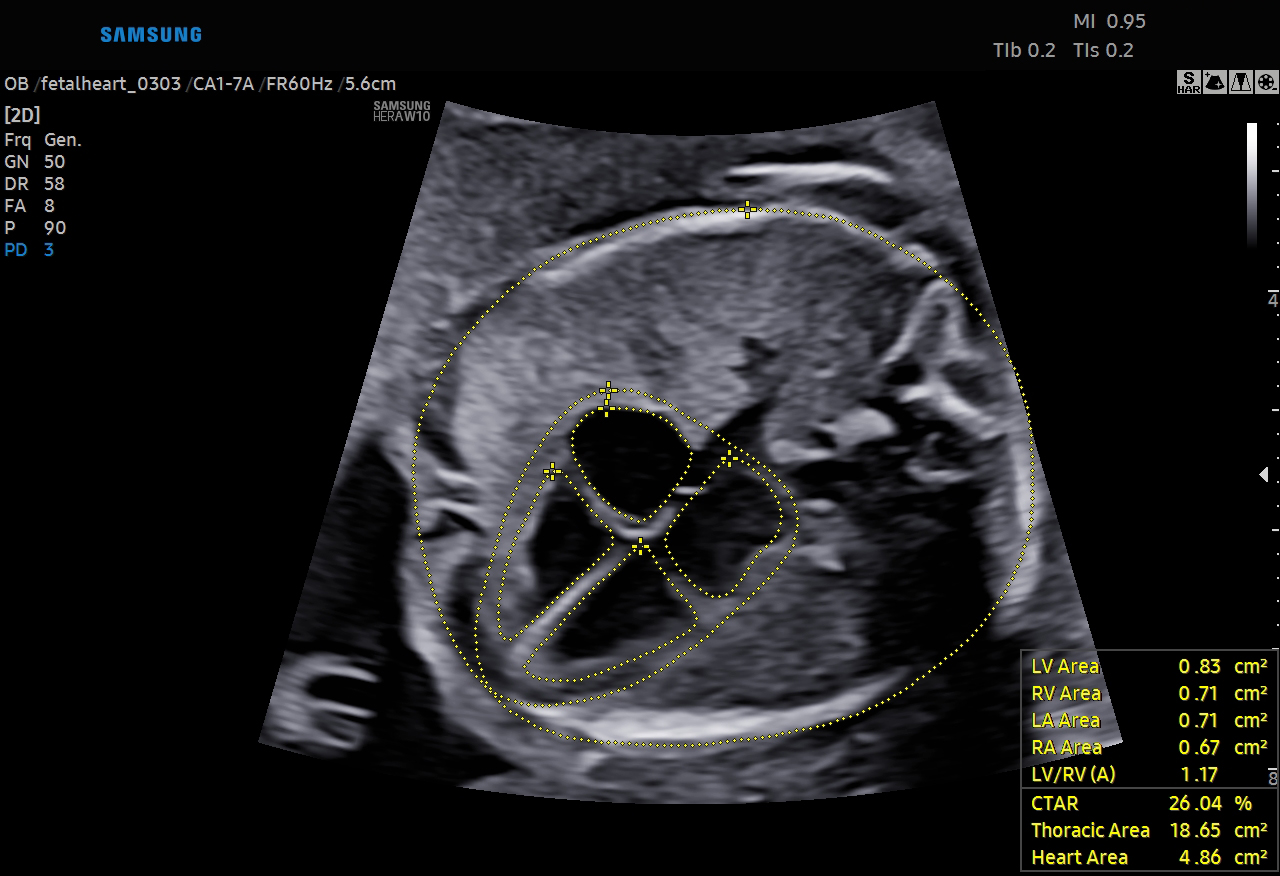

‘Biometry Solution’ recognizes images such as the fetal head, abdomen, lower extremities and others and measures the fetal growth and development while the ‘Fetal Heart Solution’ recognizes the view of the fetal heart, annotates the images and measures the necessary fetal heart structures for a thorough fetal heart anomaly assessments.

The feature automatically recognizes and annotates the anatomy of the fetal heart and displays measured values when the ‘Fetal Heart Solution’ is executed.